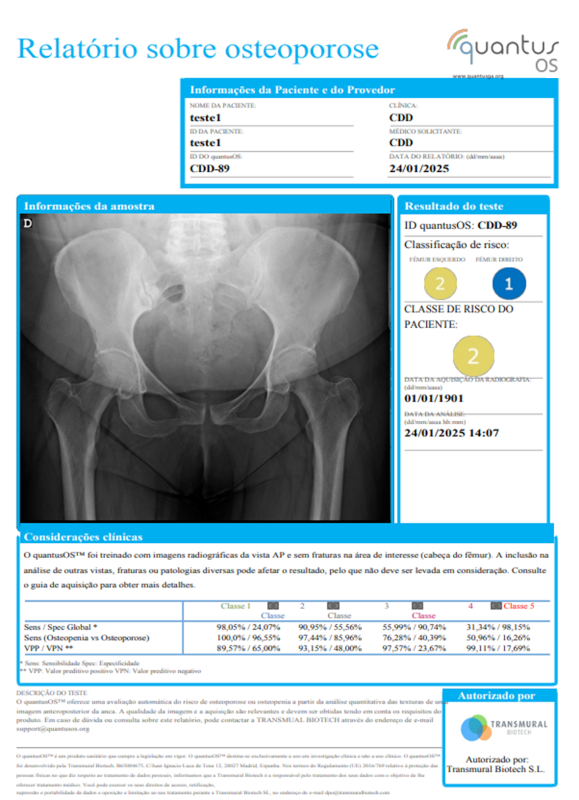

Adquirir uma radiografiaO quantusOS requer uma radiografia no formato DICOM.

Há um guia simples disponível dentro do aplicativo que mostra como realizar a aquisição da imagem.

2. Utilize o aplicativo médico quantusOS para analisar a imagem.

Esta aplicação permite enviar ao sistema a imagem que se deseja analisar. Para isso, basta seguir três passos simples para concluir a análise:

Obtenha o resultado na aplicação online em poucos minutos.

2.1 Os serviços oferecidos pela Transmural (doravante, os "Serviços") consistem em um teste não invasivo, rápido e fácil de usar para a detecção de lesões malignas de osteoporose ou osteopenia com base na análise automática de uma imagem de raio-X AP do quadril fornecida pelo Cliente.

5.1 REGIME GERAL. Os relatórios fornecidos pela Transmural ao Cliente como consequência da prestação dos Serviços indicam uma classificação de risco de que o paciente cujas imagens AP da anca correspondem terá osteoporose ou osteopenia, calculada a partir das informações fornecidas pelo Cliente. Em nenhum caso estes relatórios contêm um diagnóstico com 100% de precisão. Consequentemente, os relatórios fornecidos pela Transmural não devem, em caso algum, ser considerados como o único elemento de diagnóstico para o Cliente tomar decisões médicas. Consequentemente, o Cliente isenta a Transmural de qualquer responsabilidade derivada da tomada de decisões médicas pelo Cliente, pelo pessoal dependente ou pelos pacientes a quem correspondem as imagens fornecidas para a realização dos exames objeto dos Serviços.

5.2 A classificação de risco que a Transmural oferece em seus relatórios pode ser alterada se as imagens de raios-X fornecidas pelo Cliente não cumprirem rigorosamente as condições estabelecidas no referido "Guia de Aquisição de Imagens", que também está disponível na Plataforma.

1. Os relatórios fornecidos pela Transmural ao Usuário em decorrência da prestação dos Serviços indicam uma classificação de risco de malignidade de osteoporosis ou osteopenia correspondente às imagens AP do quadril previamente fornecidas pelo Usuário. Em nenhum caso esses relatórios contêm um diagnóstico com 100% de certeza. Consequentemente, os relatórios fornecidos pela Transmural não devem, em caso algum, ser considerados como um único elemento diagnóstico para a tomada de decisão médica do Usuário. Consequentemente, o Usuário isenta a Transmural de toda responsabilidade derivada da tomada de decisão médica por parte do mesmo, ou de terceiros sob sua responsabilidade, ou ainda dos pacientes a quem correspondam as imagens fornecidas para a realização dos testes objeto dos Serviços.

2. A classificação de risco que a Transmural oferece nos seus relatórios depende, entre outros fatores, da qualidade das imagens disponibilizadas pelo Usuário, nos termos indicados no "Guia de Captação de Imagens" já referida e disponível na Plataforma. Portanto, essas classificaçãos podem ser alterados caso as imagens do quadril fornecidas pelo Usuário não atendam estritamente às condições estabelecidas no "Guia de Captação de Imagens".